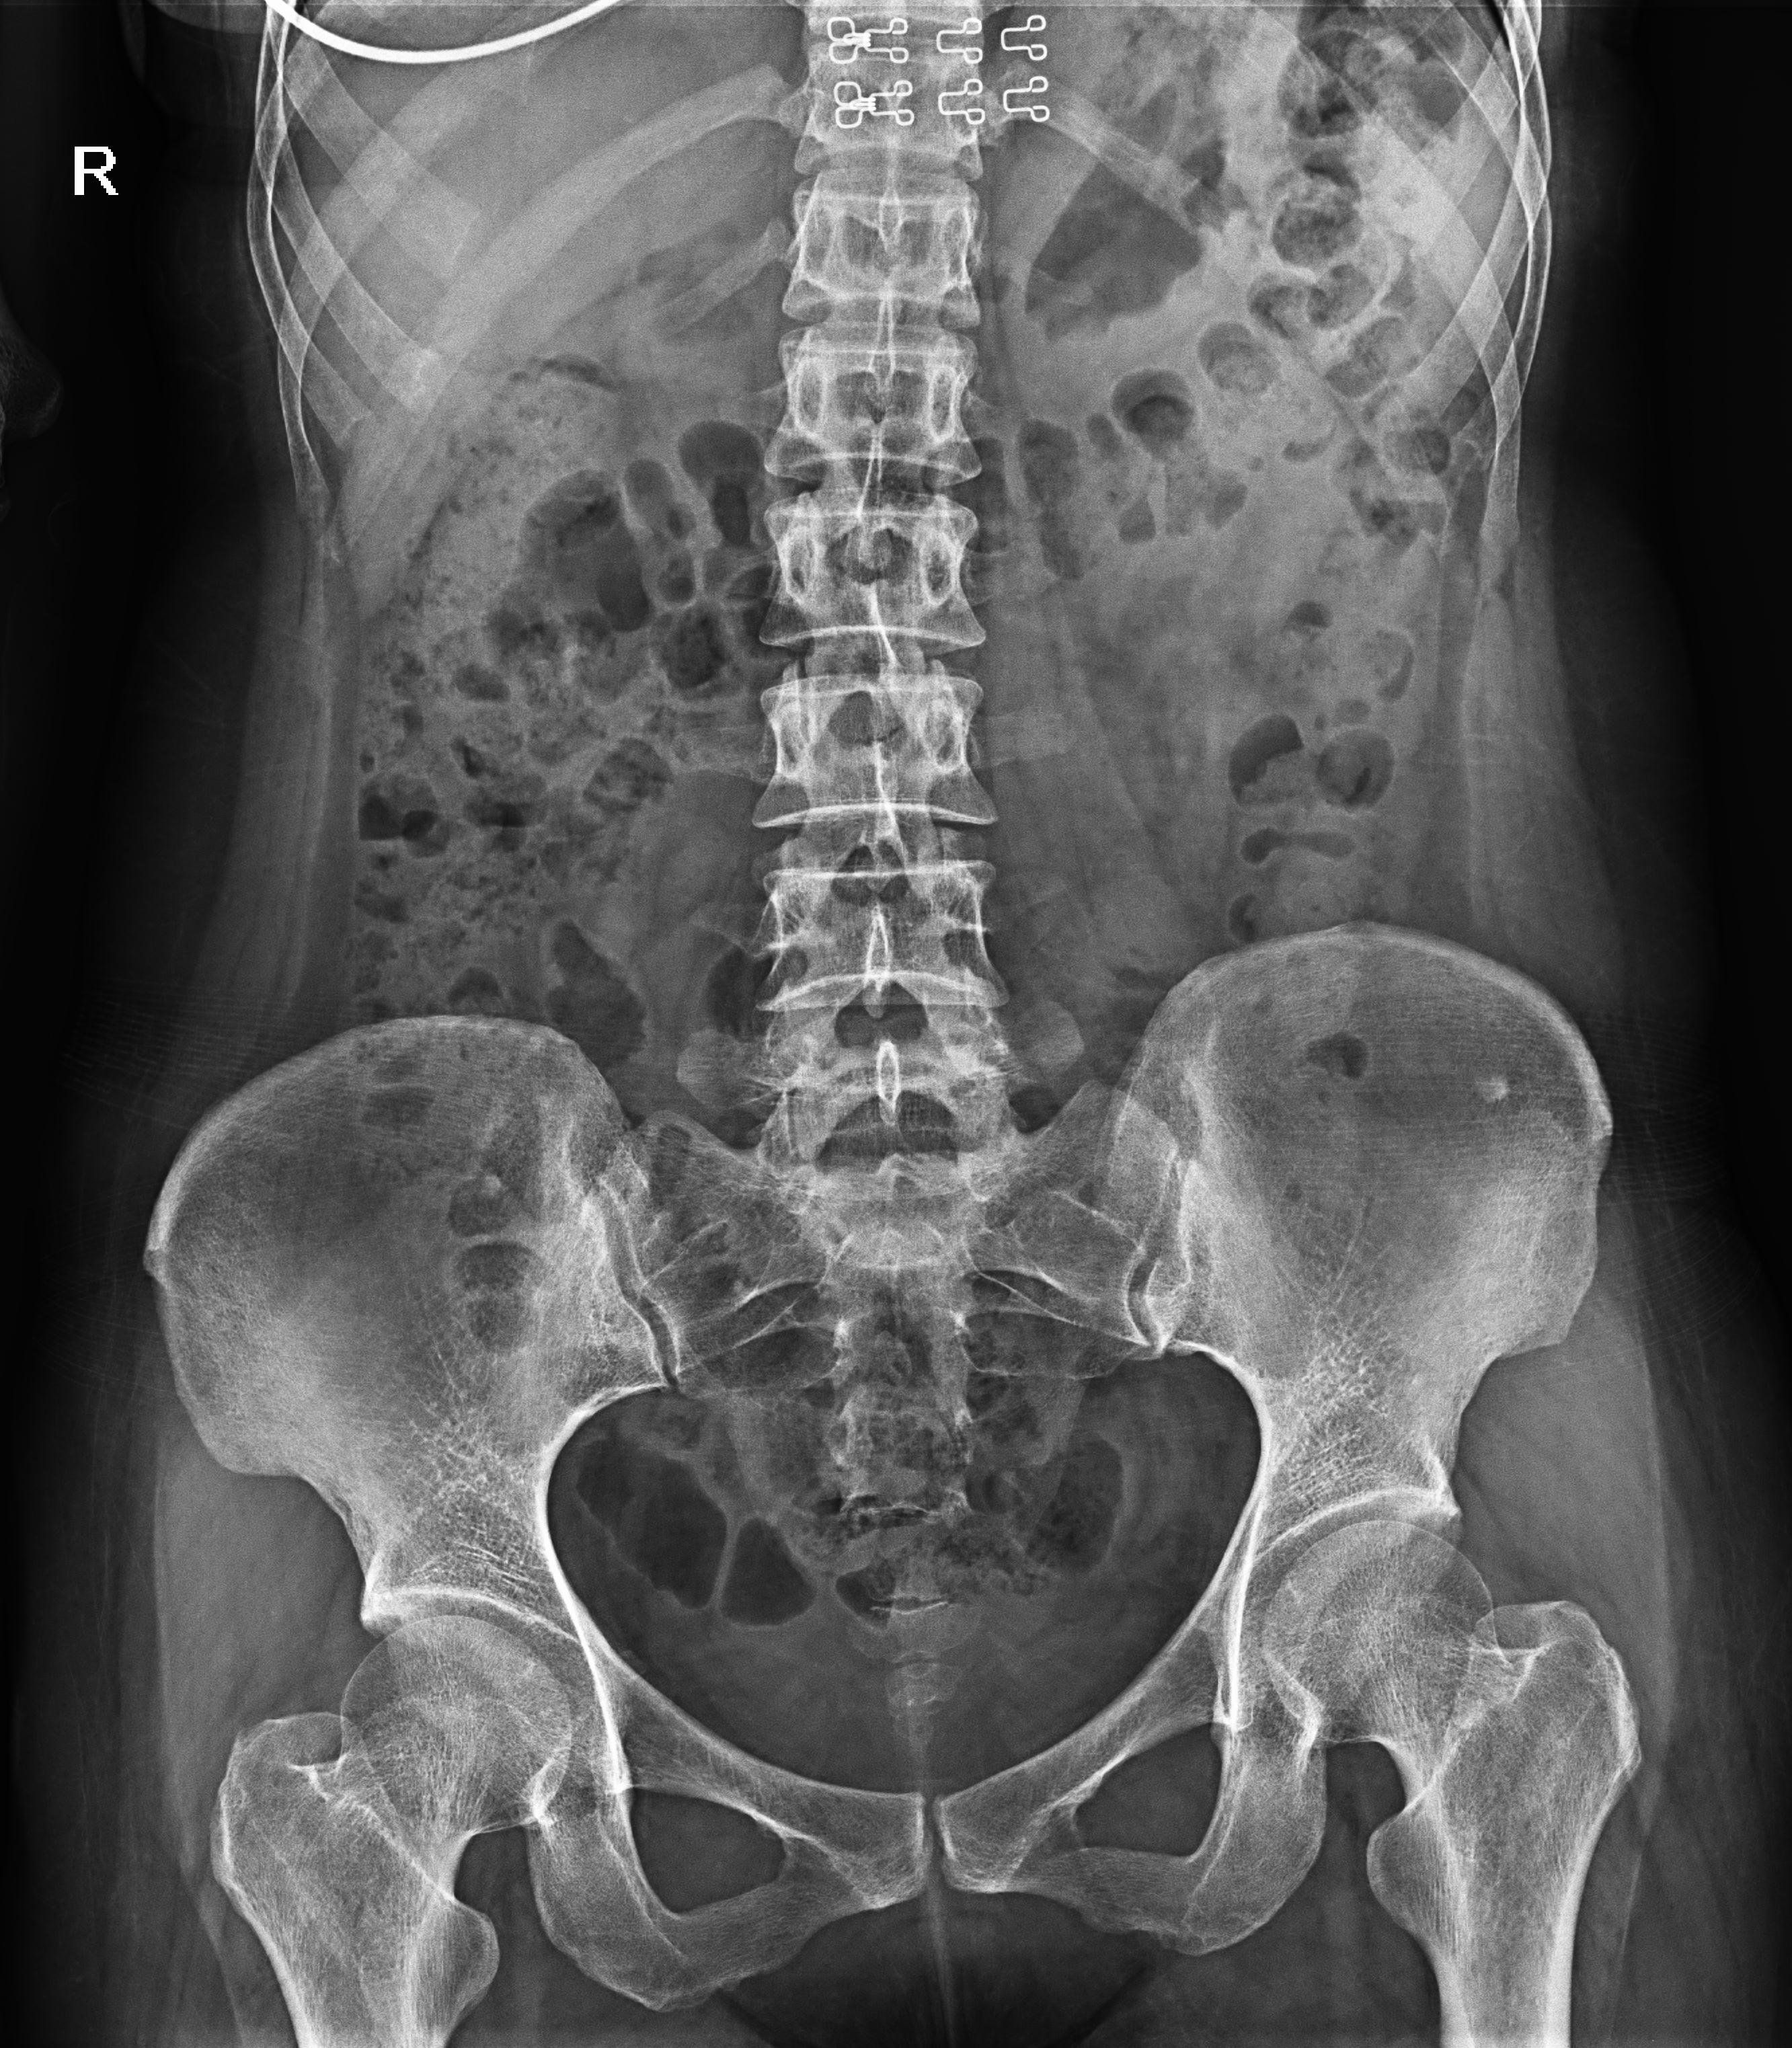

普利德醫(yī)療自主研發(fā)的新一代數(shù)字化X線透視攝影系統(tǒng),可應(yīng)用于DR攝影、數(shù)字透視、數(shù)字造影以及可視化精準(zhǔn)DR拍片等多種臨床X線檢查領(lǐng)域。

球管傾斜攝影角度-45°~45°,滿足臨床各部位各角度的攝影需求。如:髕骨軸位、頸椎正位、骶尾椎、鼻竇瓦氏位、梅氏位等部位檢查。

拉伸自如:SID電動(dòng)拉伸,最長(zhǎng)可延伸至1.8米,滿足放射科室各種拍片距離的需求。如:GBZ 70-2015職業(yè)性塵肺病的診斷標(biāo)準(zhǔn)中對(duì)胸片拍片距離1.8米的要求。

點(diǎn)片裝置移動(dòng)范圍大,無(wú)需患者移動(dòng)就能完成全身各部位的檢查;